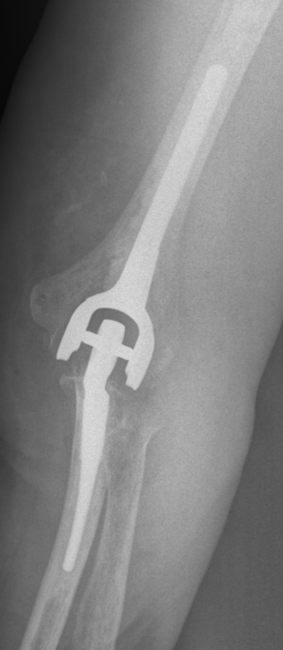

Unabhängig vom Verfahren ist das Ziel einer knorpelregenerativen Behandlung die Wiederherstellung der geschädigten Gelenkoberfläche. Verlaufen alle gelenkerhaltenden Therapien erfolglos und können die Schmerzen des Patienten nicht verringern, ist als letzter Schritt der Einsatz eines künstlichen Ellenbogengelenks (Ellenbogenprothese) möglich.

Diesen Schritt bespricht der Orthopäde ausführlich mit dem Patienten, da zwar häufig eine deutliche Schmerzreduktion und verbesserte Beweglichkeit erreicht wird, jedoch das Gelenk zukünftig nur noch gering belastet werden sollte, um Lockerungen zu vermeiden.